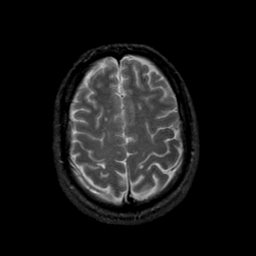

MR Study #23, January 26, 1992 -- Slice #39